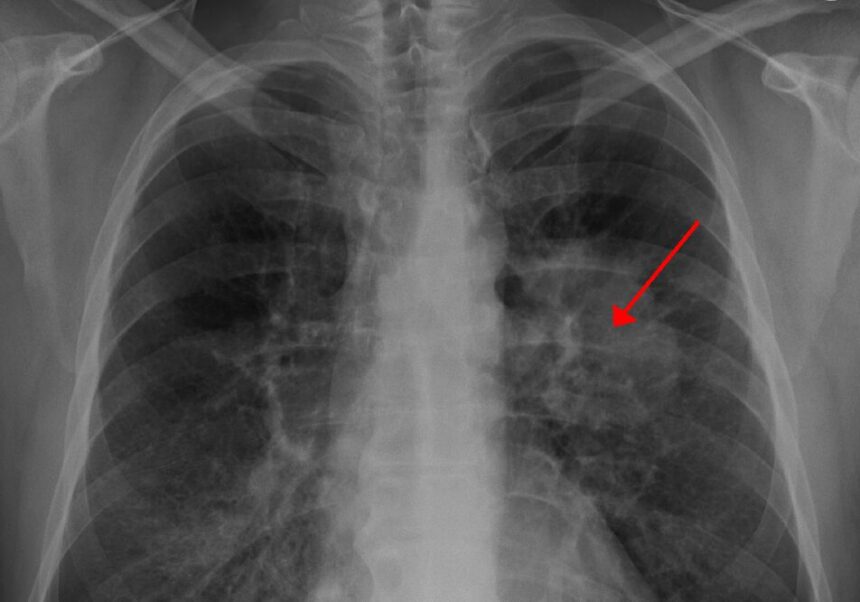

Dikatakan bahwa faktor risiko kanker paru adalah pajanan senyawa asbes, rokok dan polusi udara. “Pajanan senyawa asbes dalam jangka panjang memang menjadi salah satu faktor risiko timbulnya kanker paru dan kanker pada selaput pleura,yakni Mesothelioma,” tambahnya.